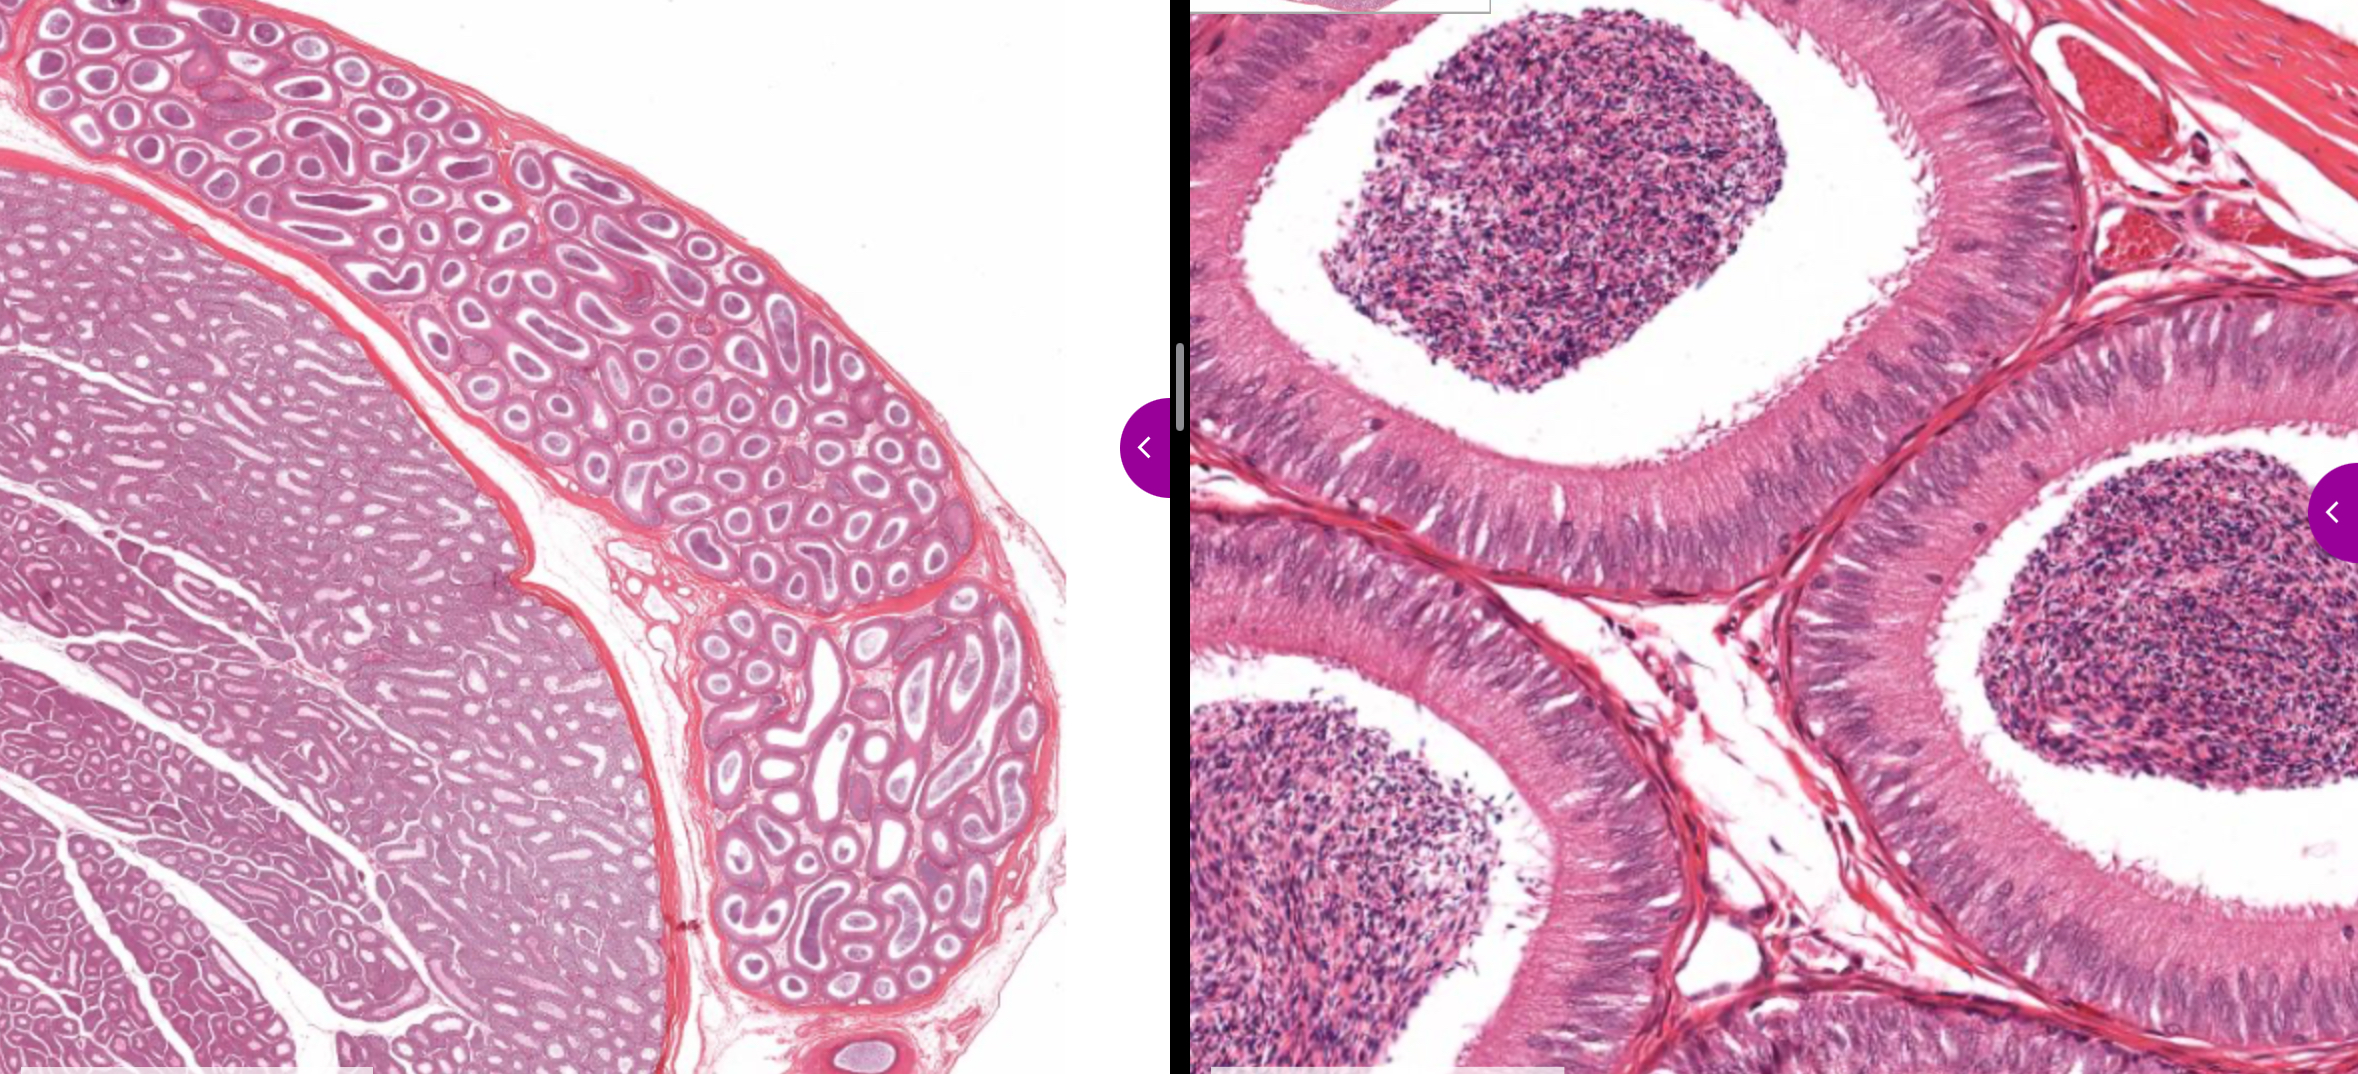

efferent ductule

all parts

epididymis

histo

of epididymis

head

body

tail